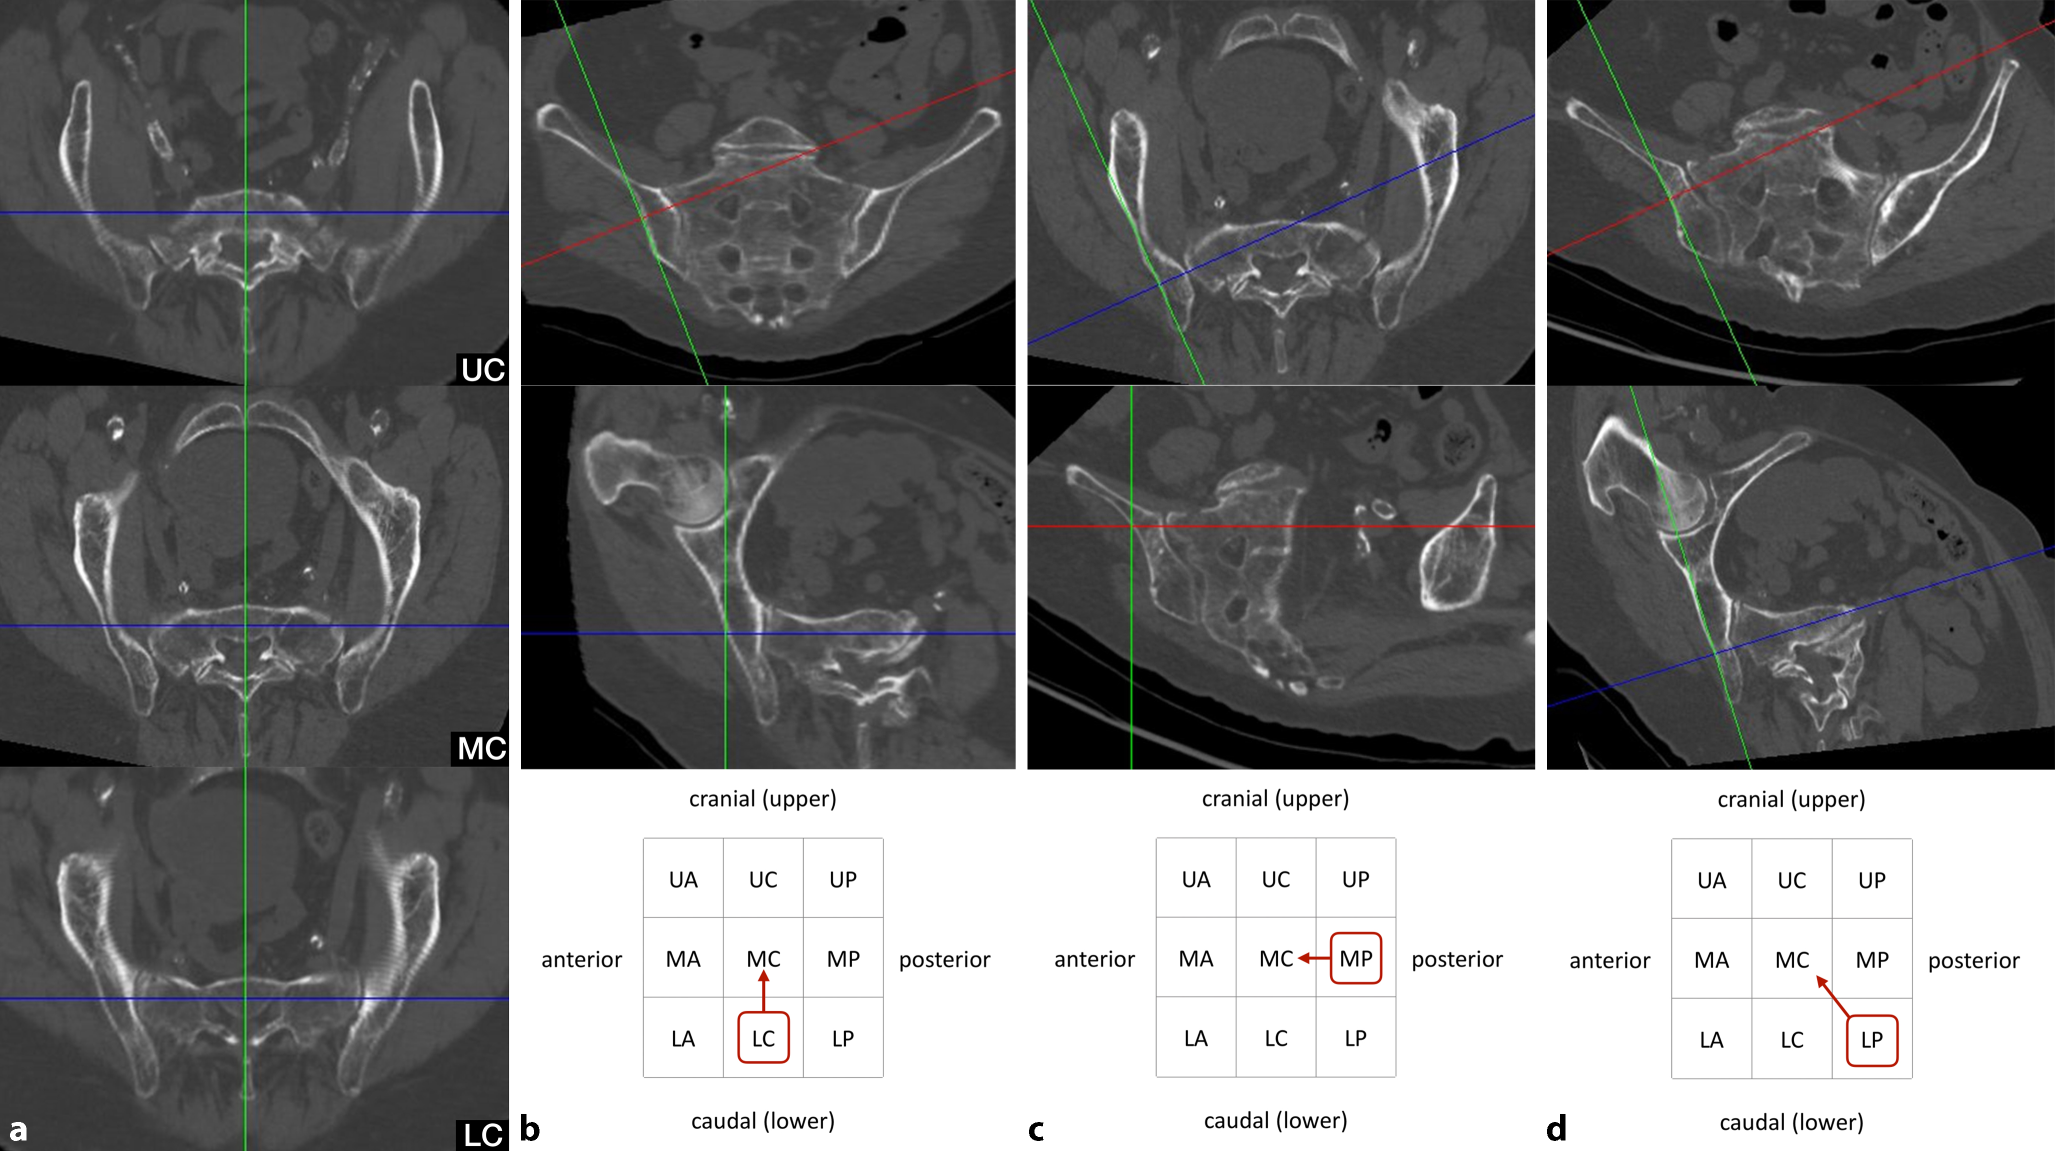

Fourth step—assessing oblique screw trajectories

The term “sacral dysmorphism” is widely used and several radiographic characteristics of dysmorphic sacral anatomy have been defined [12]. Nevertheless, a clear and generally accepted definition is still lacking. In our opinion, the lack of safe osseous corridors for transverse screw trajectories in S1 may be a reasonable definition of “sacral dysmorphism”. Accordingly, this applies especially for patients with ascending corridors and notches. In the present case of an ascending type (Fig. 4a) there is no osseous corridor for transverse trajectories in the upper (UC), middle (MC) and lower third (LC).

Fig. 4

Fourth step of preoperative work-up: assessing oblique screw trajectories. a Sacral dysmorphism, b–d three main options for oblique S1 screw trajectories. Blue line coronal axis, green line sagittal axis, red line horizontal axis, red circumscribed letters represent the zone for screw starting point, red arrows indicate the direction of the oblique screw trajectory

Bild vergrößern

However, there are obviously numerous options for oblique trajectories in S1 in the presence of sacral dysmorphism. Safe oblique trajectories typically run from posterior to anterior in the inlet view and from caudal to cranial in the outlet view. It is advisable to assess an oblique trajectory, which runs oblique in a single plane only and transverse in the orthogonal plane, as this facilitates intraoperative two-dimensional fluoroscopic control. In some cases, however, oblique trajectories in both the inlet and outlet view are inevitable. Accordingly, there are three main options for oblique S1 screw trajectories as shown in Fig. 4b–d:

First option (Fig. 4b).

In the outlet view, the intersection of the sagittal axis (green line) and the horizontal axis (red line) is moved to an optional starting point in the lower third on the lateral cortex of the ilium. The horizontal axis is then rotated cranially to reach the middle third in the midsagittal plane. Without any further adjustments in the inlet view, both views now show a safe osseous corridor. The screw trajectory is oblique in the outlet view (“outlet-oblique”), but transverse in the inlet view (“inlet-transverse”) and runs from LC to MC.

Second option (Fig. 4c).

In the inlet view, the intersection of the sagittal axis (green line) and the coronal axis (blue line) is moved to an optional starting point in the posterior third on the lateral cortex of the ilium. The coronal axis is then rotated anteriorly to reach the central third in the midsagittal plane. Without any further adjustments in the outlet view, both views now show a safe osseous corridor. The screw trajectory is oblique in the inlet view (“inlet-oblique”), but transverse in the outlet view (“outlet-transverse”) and runs from MP to MC.

Third option (Fig. 4d).

This option is required in the presence of sacral dysmorphism and no safe corridor with an oblique trajectory in a single plane. The horizontal axis (red line) is adjusted in the outlet view and the coronal axis (blue line) is adjusted in the inlet view. The screw trajectory is oblique in the inlet view (“inlet-oblique”) and oblique in the outlet view (“outlet-oblique”) and runs from LP to MC.